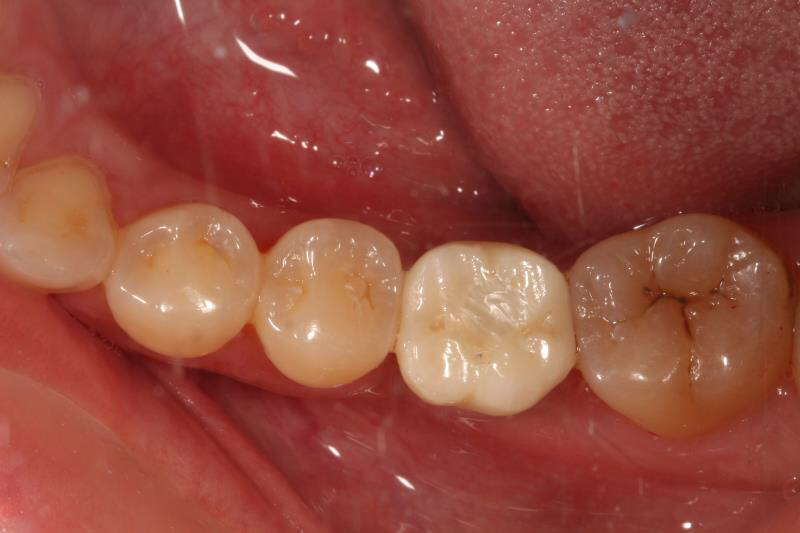

今天给大家介绍一个单颗后牙种植+局部正畸联合治疗病例。

患者年轻女性,后下6残根,因未及时修复,5、7号牙向6号牙倾斜,导致了修复空间不足。按照常规治疗方案,会损伤两侧的健康牙齿,得不偿失,所以我们为她采用了正畸+种植联合治疗方案。